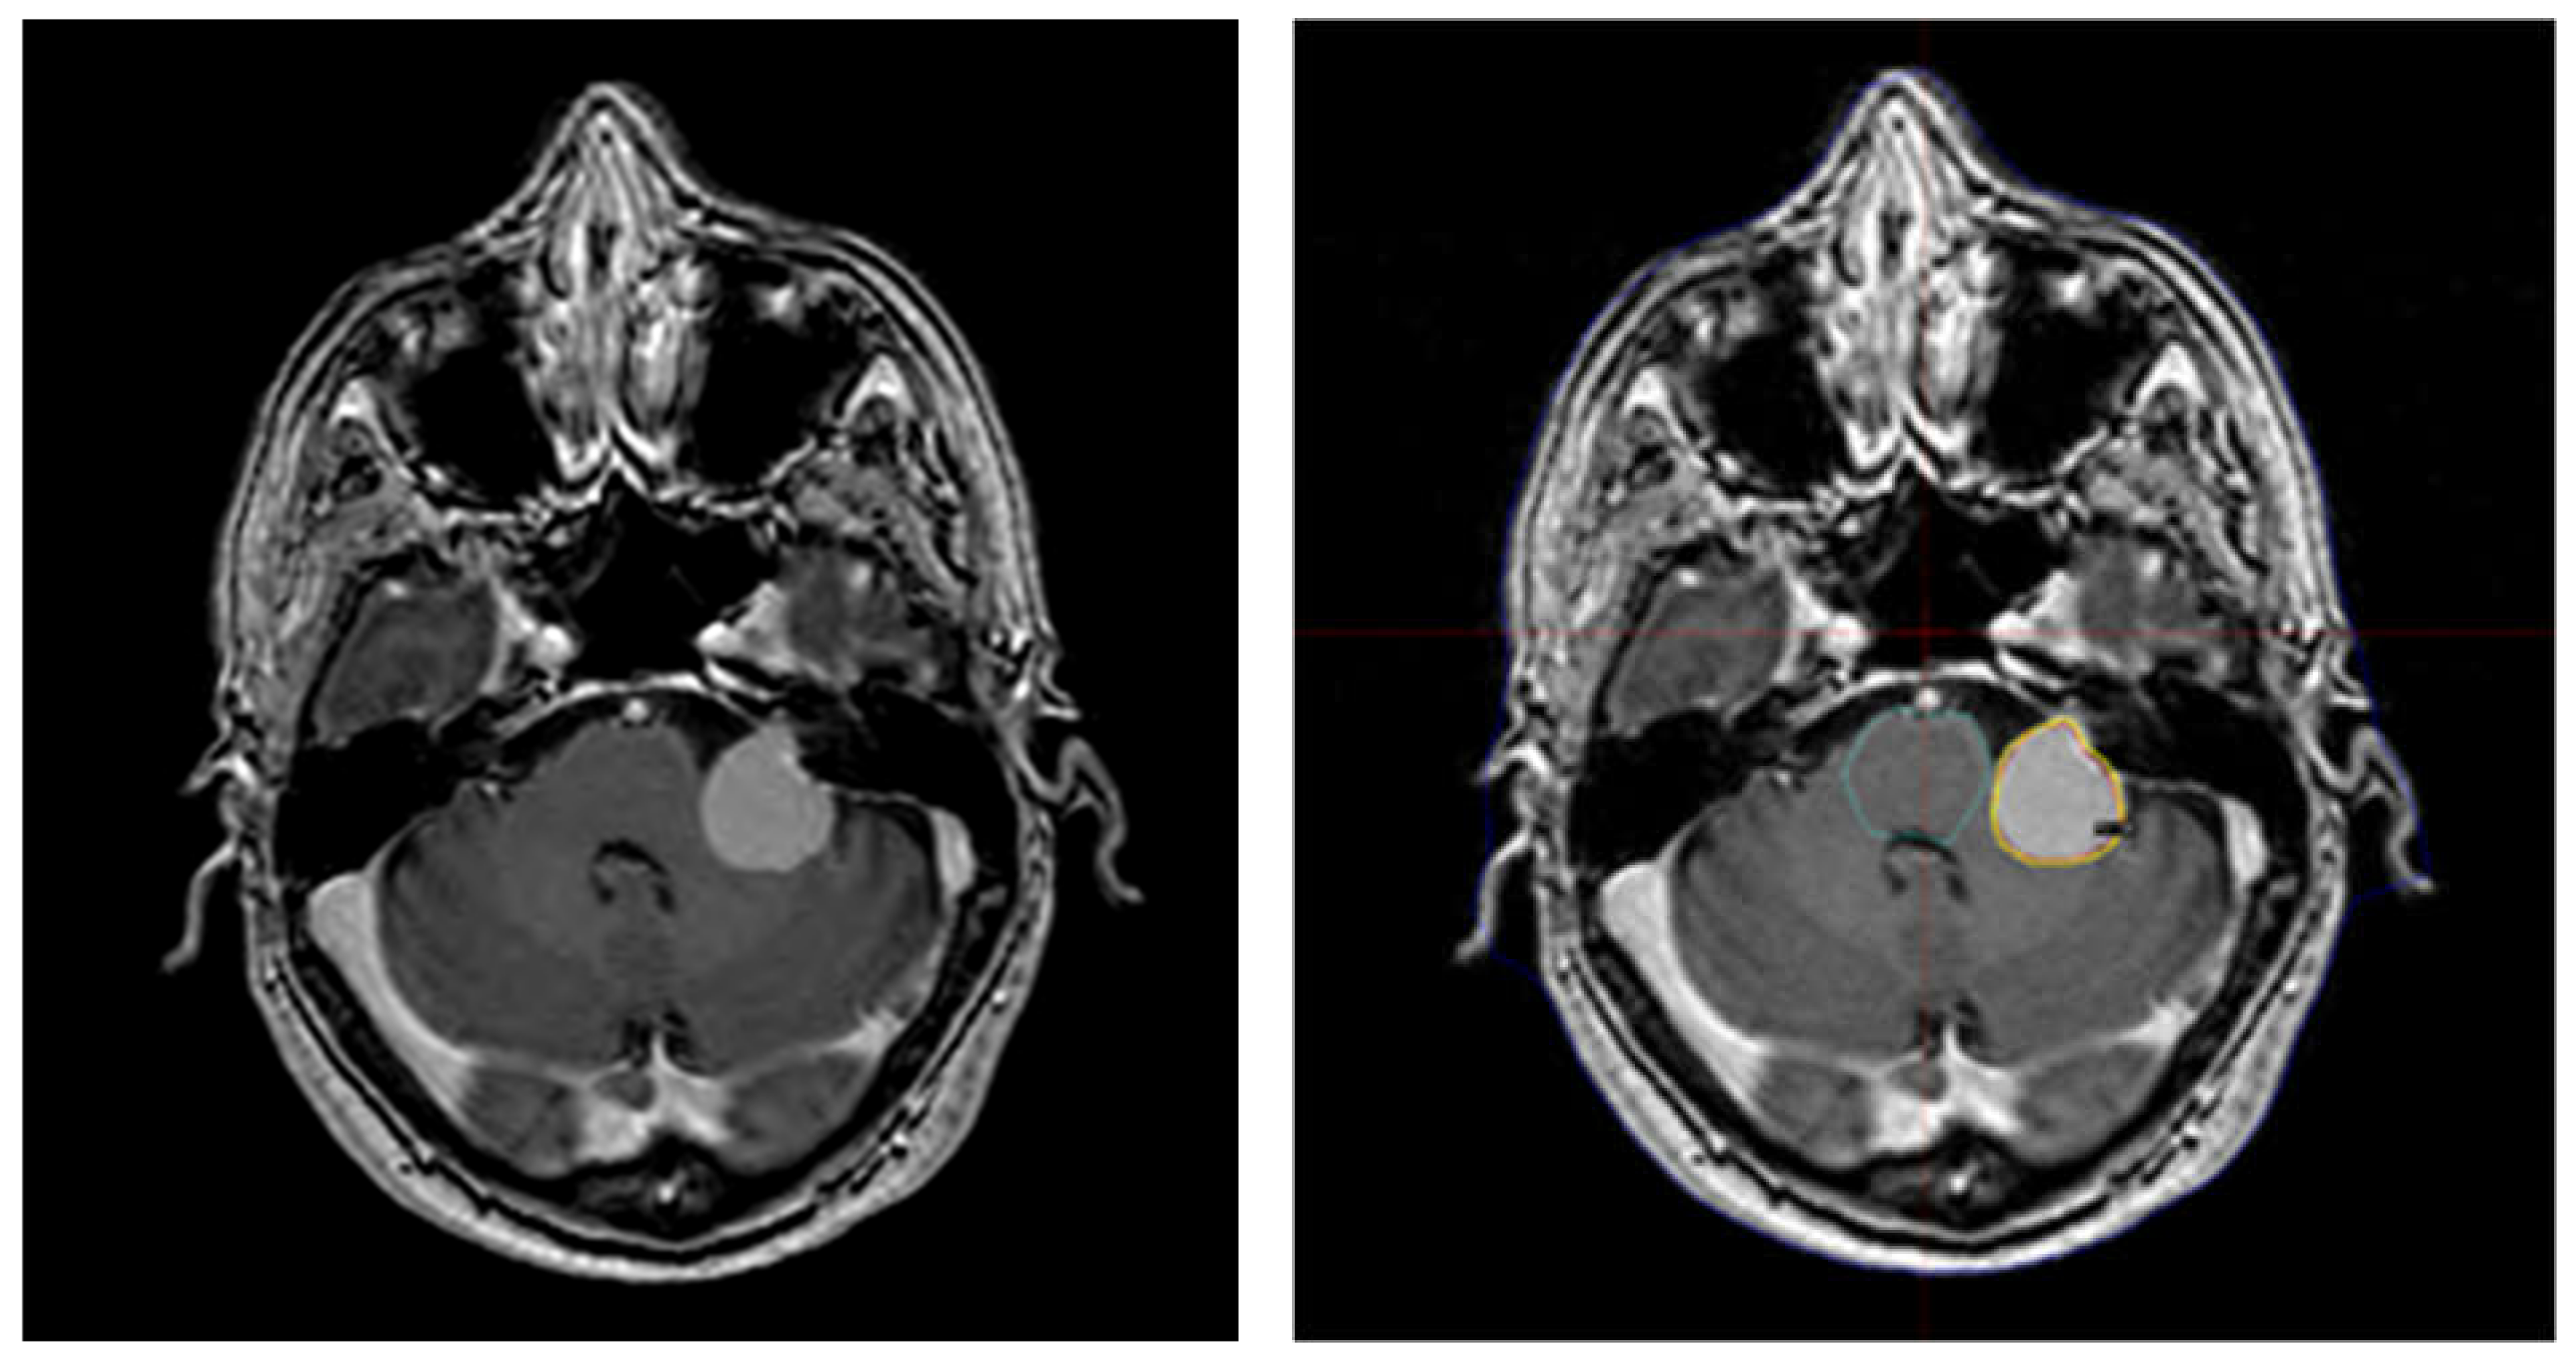

| 2 | 56 | female | left cerebellar | 1.310 | 9.41200765 | 14 | 3.5 | 18 | 2.6 | −26% | 14.0 |

| 16 | 52 | female | left cerebellar | 2.35 | 54.3340367 | 13 | 2.9 | 13.0 | |||